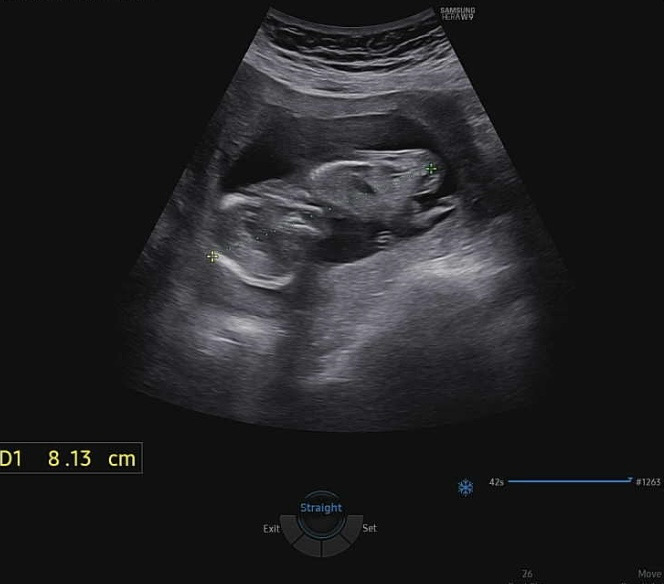

아들일까요? 딸일까요?

14주 2일차 입니다. 엎드려있는 초음파라 성별 구별하기 힘드네요;;ㅎㅎㅎ

아들인거 같아요